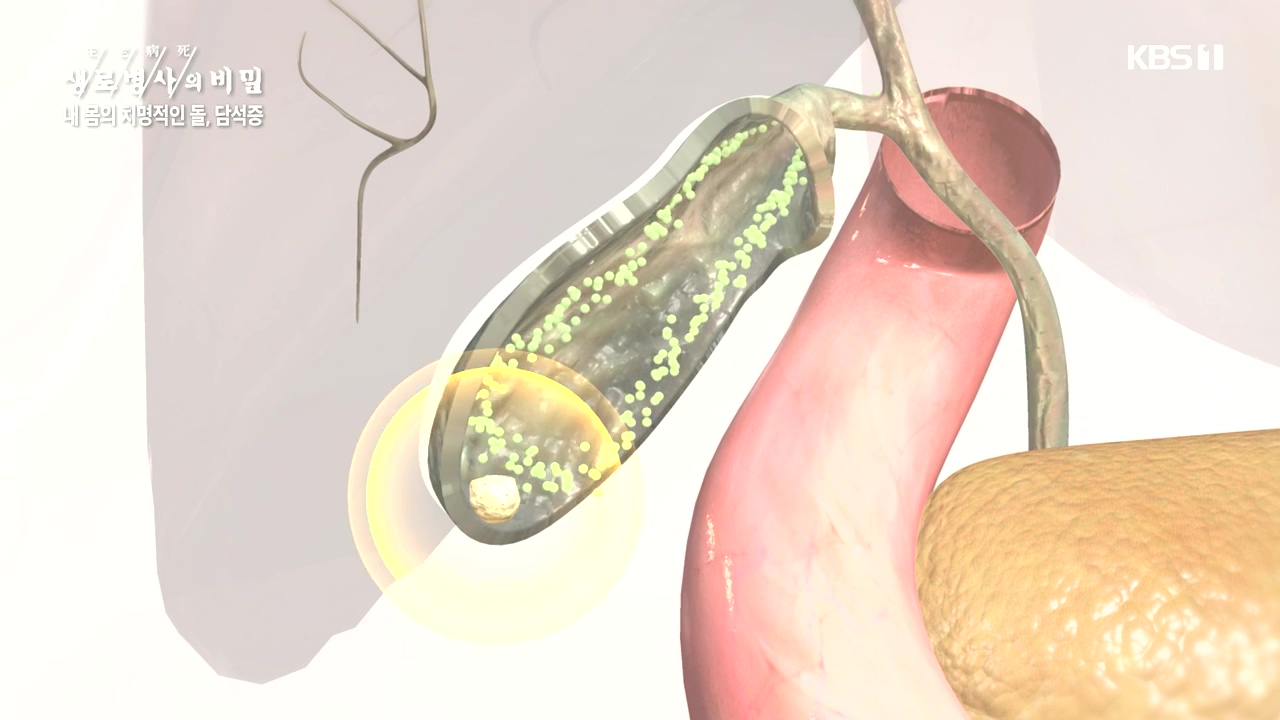

[박은철 기자] 담석증은 지방 소화를 돕는 담낭(쓸개)에 담즙이 굳어서 돌처럼 덩어리가 생기는 질환이다. 주로 쓸개주머니라 불리는 담낭 안이나...

내 몸의 치명적인 돌 담석증